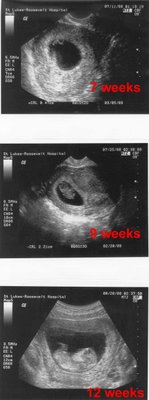

By the way, I think these ultrasound pix probably tells it all. We’re expecting! The docs say the baby looks good so far. Giselle’s at high risk because she’s diabetic so we’re going to the various doctors at least once a week right now. Baby is due in late Feb.